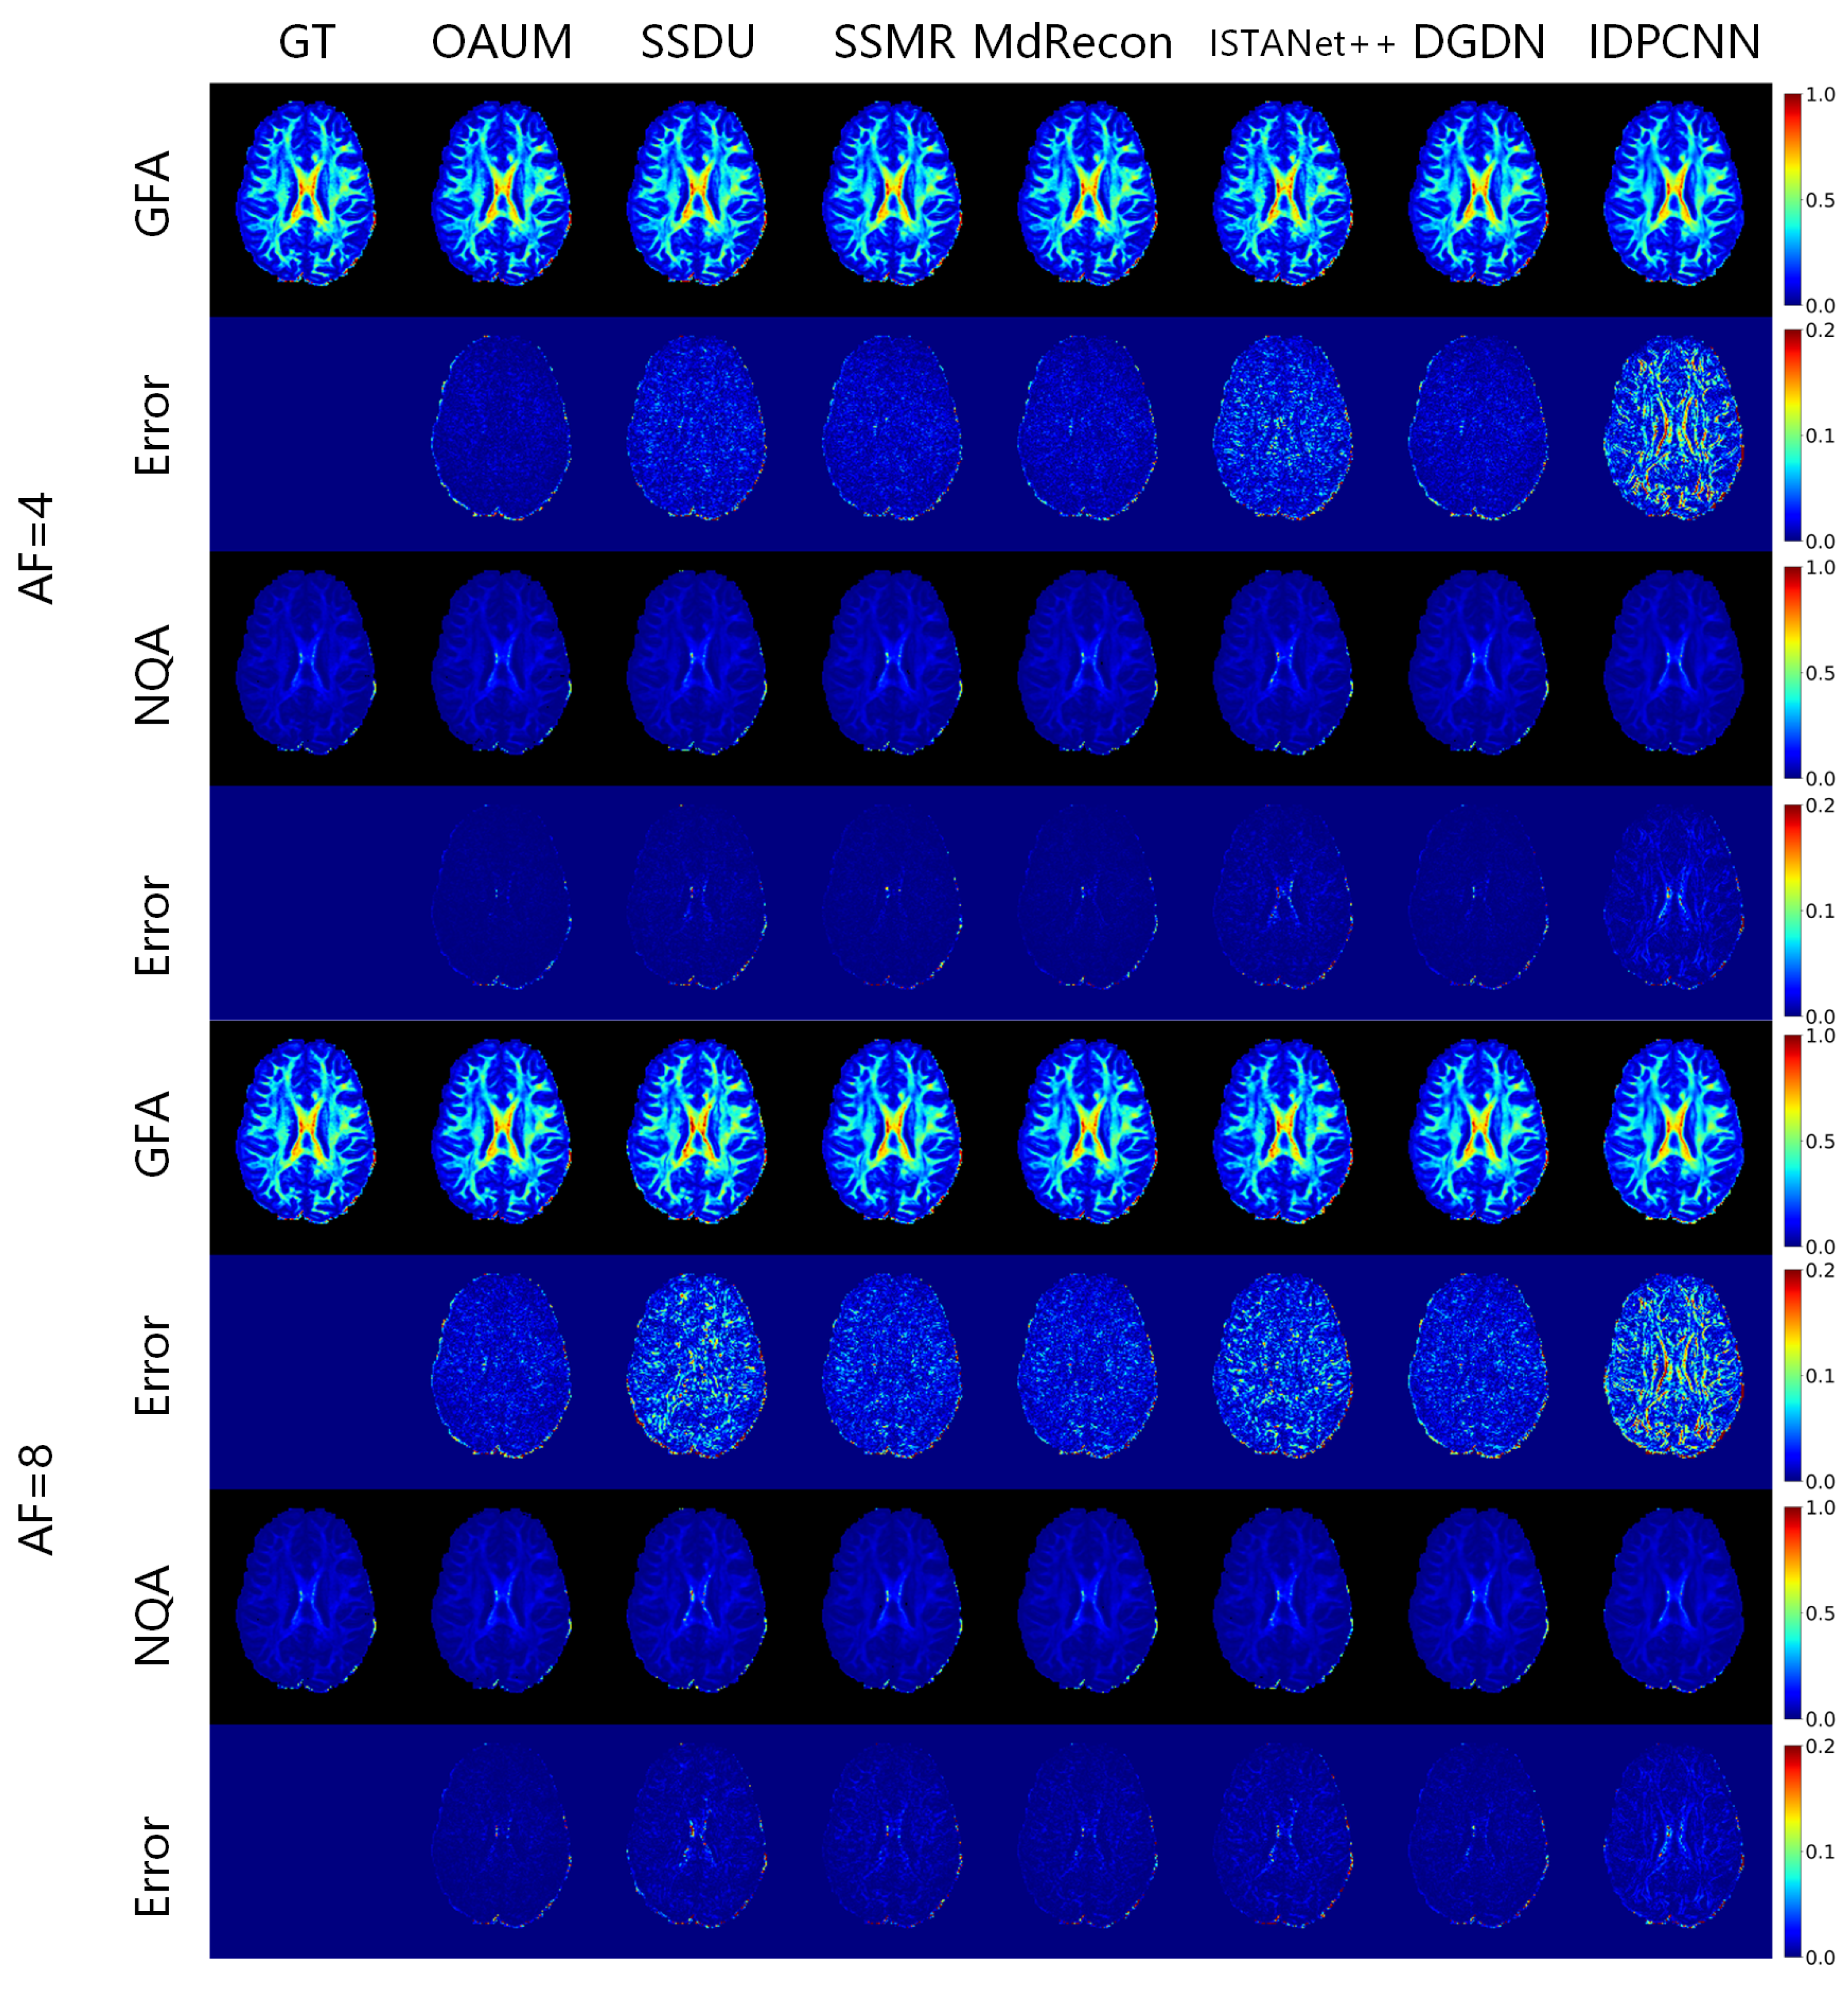

Based on the reconstruction of fiber orientation using HARDI, we calculated the generalized fractional anisotropy (GFA) and normalized quantitative anisotropy (NQA) under different acceleration sampling factors to characterize the diffusion of water molecules in tissues, as shown in Figure 7. The given GFA and NQA results, along with corresponding residual maps, indicate that all models except IDPCNN and ISTANet++ can reconstruct diffusion parametric maps well. Our OAUM model had the closest reconstructed GFA and NQA to the real results, with minimal residual values compared to the other models. Although the NQA image reconstructed by DGDN was close to our method, its reconstructed GFA image was slightly worse. Table 4 and Table 5 provide quantitative indicators that show that, regardless of whether it is at a 4-fold or 8-fold acceleration factor, the OAUM model obtained optimal quantitative evaluation results for both GFA and NQA, i.e., with the lowest RMSEs and the highest PSNRs and SSIMs. This implies that our proposed strategy ensures accuracy in HARDI parametric maps reconstruction under undersampling conditions.

Figure 7. The parametric maps estimated from DWIs at different acceleration factors.